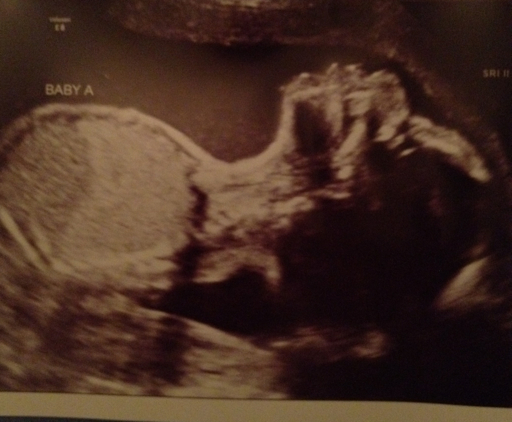

I had an appointment today with the specialist.  Both babies weigh approximately 1lb, 7oz and they are both head down right now.  I really hope they like that position and stay in it!  As usual, they were super active.  The u/s tech always seems surprised at this.  Addyson was arching her head back, acting as if she can't wait to get out and stretch.  Her head is closest to my cervix which certainly explains a lot.

Here's Addyson: